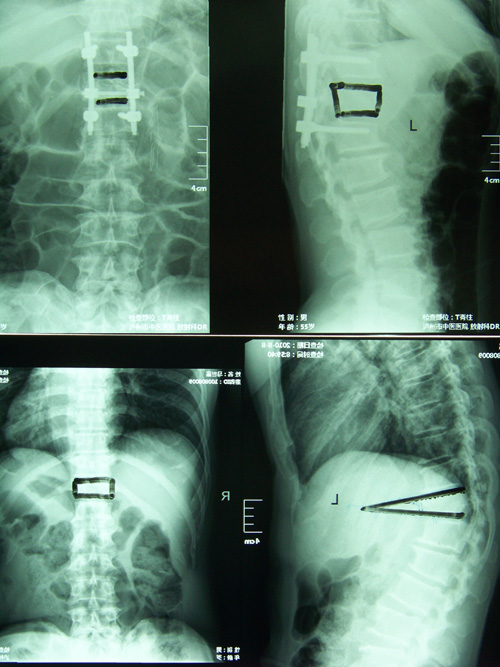

• 我科成功開展椎體形成術(shù)

• ????????????????????????????????? 骨傷一科成功開展經(jīng)皮穿刺椎體成形術(shù)???????????????????????????????????????????????? 骨傷一科 肖言潔??? 骨傷一科近日成功開展了高齡患者胸腰椎壓縮性骨折經(jīng)皮穿刺椎體成形術(shù),該手術(shù)方式...